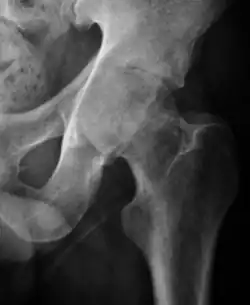

Projectional radiography ("X-ray") is the first imaging technique of choice in hip pain, not only in older people with suspected osteoarthritis but also in young people without any such suspicion. In this case plain radiography allows categorization as normal hip or dysplastic hip, or with impingement signs, pincer, cam, or a combination of both.[1]

X-Ray

Projectional radiography ("X-ray") is currently useful not only in older people in whom osteoarthritis of the hip is suspected but also in younger people without osteoarthritis, who are being evaluated for femoroacetabular impingement (FAI) or hip dysplasia.[1]

Plain radiography allows us to categorize the hip as normal or dysplastic or with impingement signs (pincer, cam, or a combination of both). Besides these, pathologic processes like osteoarthritis, inflammatory diseases, infection, or tumors can also be identified (Figure 1).[1]